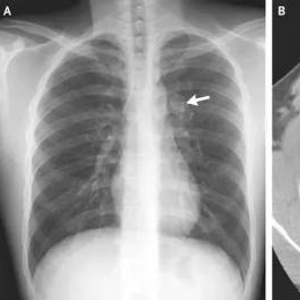

在甲状腺疾病中,恶性病变(如甲状腺癌)和良性病变(如结节性甲状腺肿)均可能存在钙化灶。甲状腺钙化大致可分为微钙化、粗大钙化和边缘环形钙化。

微钙化通常小于2毫米,表现为点状、针尖样、沙粒状钙化,在甲状腺乳头状癌患者中常见,但也并非有了这种钙化就是癌;粗大钙化表现为片状、弧形或其他不规则形钙化,通常发生在良性结节性甲状腺肿患者中;边缘环形钙化,一般出现在良性结节中。